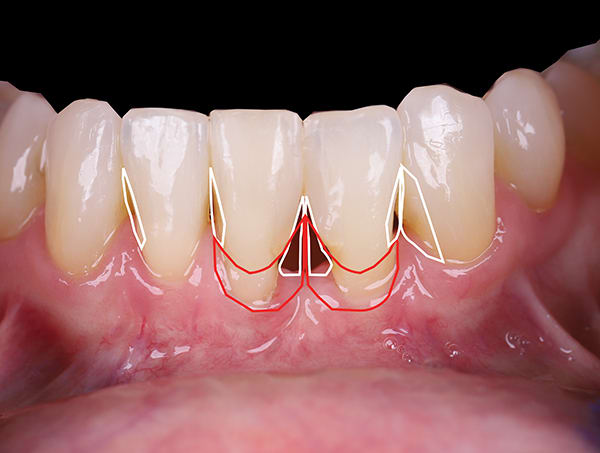

Black triangles in cervical embrasure areas are unesthetic and often cause patients to have difficulty with phonetics and hygiene. A 66-year-old woman presented to the periodontal office of Dr. Jason Stoner with excessive bleeding in the mandibular anterior region. She had a history of trauma to teeth Nos. 24 and 25 years prior, which were endodontically treated at the time of injury. Dr. Stoner's evaluation revealed a large resorptive defect on the distal extent of tooth No. 24. After considering different treatment options, the patient opted for removal of No. 24 and orthodontic therapy to achieve space closure post-extraction. Prior to removal of the tooth, Drs. James Hutta and Jeff Price were added to the treatment team to assist with orthodontics. Dr. Stoner extracted tooth No. 24 without complication, and the orthodontic phase took approximately 18 months. Upon completion of orthodontics a large residual black triangle remained between teeth Nos. 23 and 25. At this time, the patient's previous restorative dentist placed composite bonding, which the patient was not happy with. She then was referred to the author's office for evaluation of the residual Miller Class III defect. Exploiting the many benefits of bioactive Giomer Technology (Shofu, shofu.com), the author developed a treatment plan that would utilize both pink Giomer and white composite to satisfy the treatment objectives.

Pre-treatment digital blueprints assist the patient and treatment team in determining positioning and possibilities.